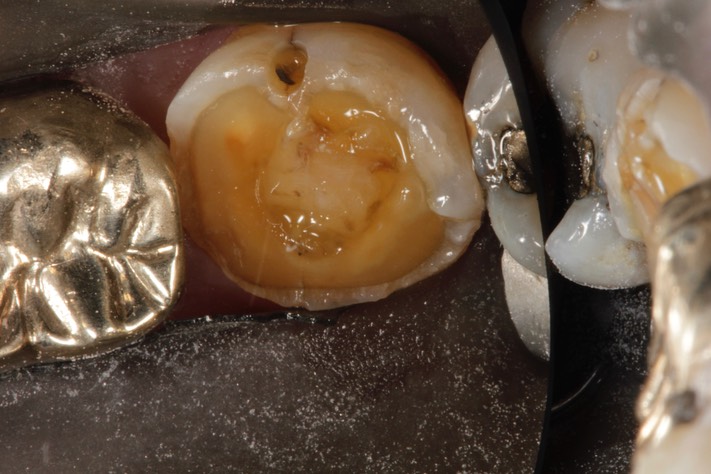

Larry Fujioka #18 caries removal